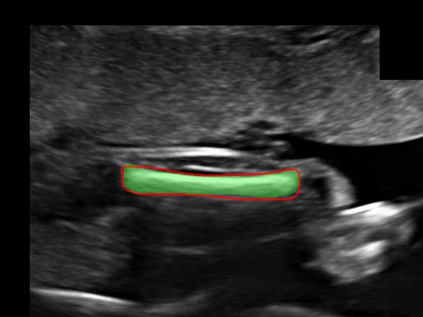

In this paper, we propose an end-to-end multi-task neural network called FetalNet with an attention mechanism and stacked module for spatio-temporal fetal ultrasound scan video analysis. Fetal biometric measurement is a standard examination during pregnancy used for the fetus growth monitoring and estimation of gestational age and fetal weight. The main goal in fetal ultrasound scan video analysis is to find proper standard planes to measure the fetal head, abdomen and femur. Due to natural high speckle noise and shadows in ultrasound data, medical expertise and sonographic experience are required to find the appropriate acquisition plane and perform accurate measurements of the fetus. In addition, existing computer-aided methods for fetal US biometric measurement address only one single image frame without considering temporal features. To address these shortcomings, we propose an end-to-end multi-task neural network for spatio-temporal ultrasound scan video analysis to simultaneously localize, classify and measure the fetal body parts. We propose a new encoder-decoder segmentation architecture that incorporates a classification branch. Additionally, we employ an attention mechanism with a stacked module to learn salient maps to suppress irrelevant US regions and efficient scan plane localization. We trained on the fetal ultrasound video comes from routine examinations of 700 different patients. Our method called FetalNet outperforms existing state-of-the-art methods in both classification and segmentation in fetal ultrasound video recordings.